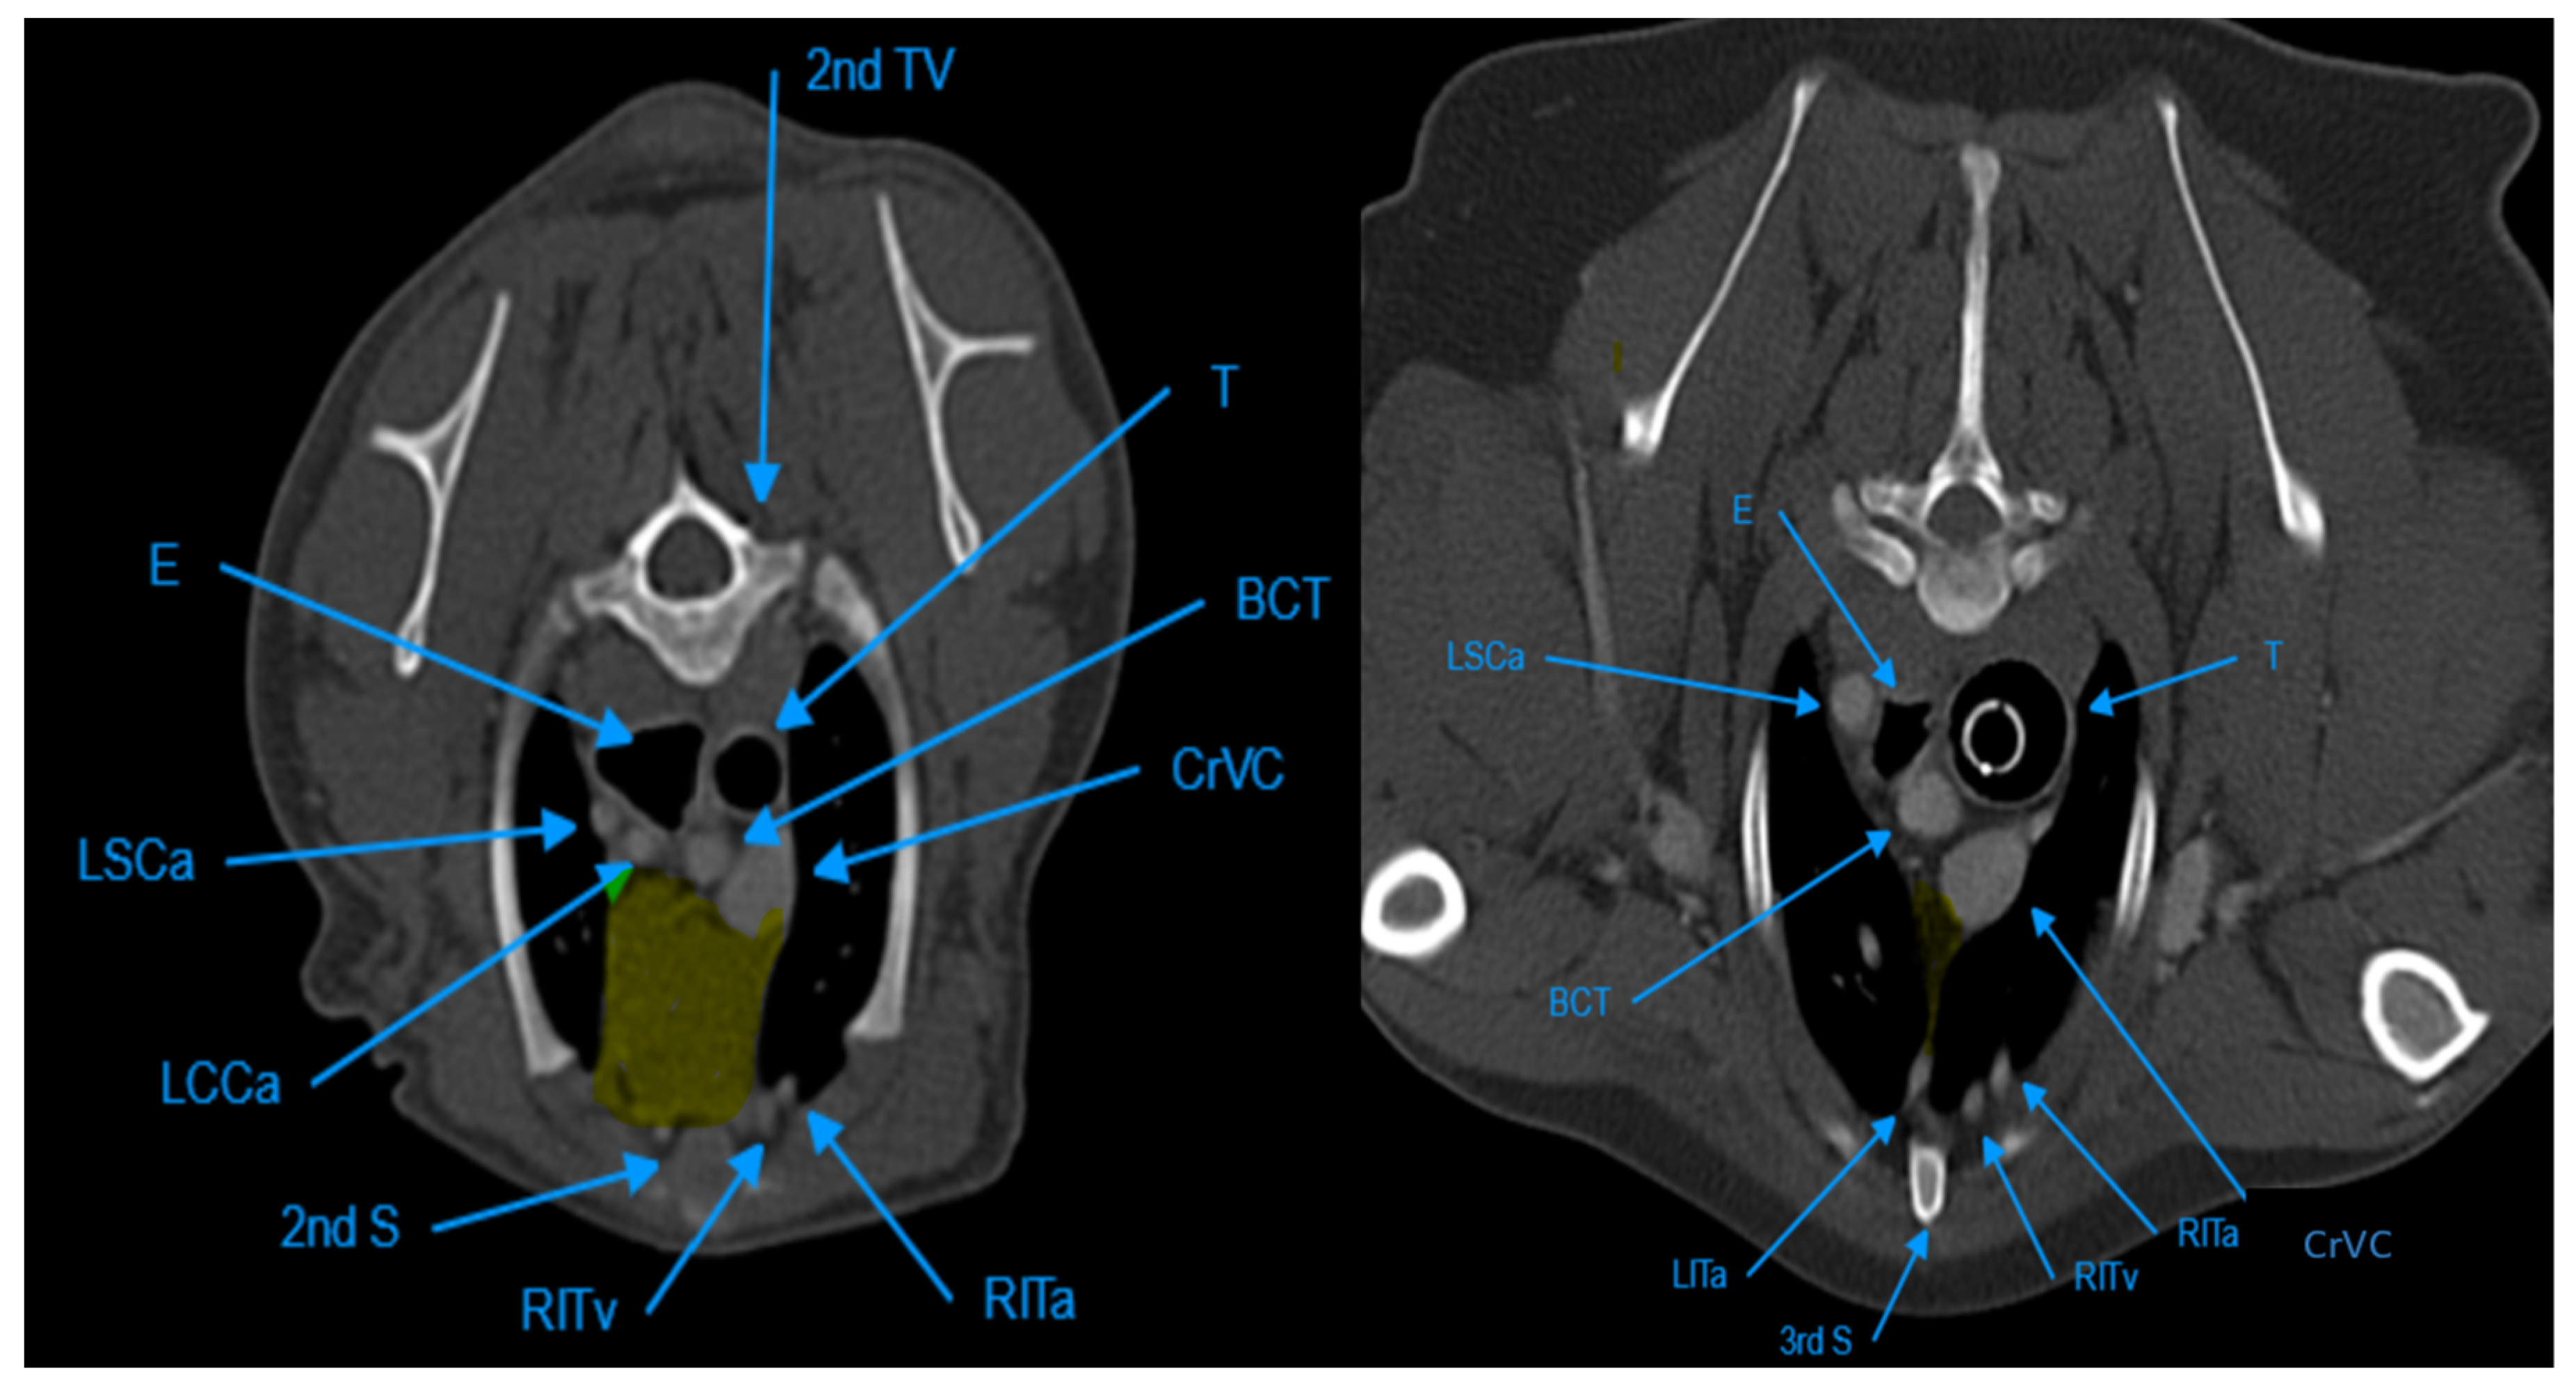

The thymus glands were evaluated in the first step to determine whether they were visible or not. Non-visible thymus glands were those with complete degeneration seen with fat attenuation and not distinguishable from mediastinal fat. After that, a grading system for thymic tissue appearance was used based on its predominant component (grade-0: totally fatty replacement of the thymus (non-visible) and could not differentiate from mediastinal fat; grade-1: more than 50% fatty replacement of the thymus; grade-2: more than 50% soft tissue component in the thymus; grade-3: totally soft tissue component in the thymus (Figure 1). After grading the thymus, the attenuation (CT number) of thymic tissue in plain and contrast-enhanced images was measured. For this purpose, a round-shape region of interest (ROI) with a surface equal to 75 mm2 was considered in the widest part of the organ for large thymus glands (Figure 2) and a smaller ROI for small thymus glands. Then pre- and post-contrast Hounsfield Units (HU) were compared for each patient individually and also between groups for evaluating the pattern of attenuation alteration.

Figure 1. Demonstration of Post-contrast Transverse CT scan images for Different Grades of Thymus. Picture (a) shows a Visible Grade-3 Wedge-shape Left-sided Thymus in a 4-month-old Male Mixed-breed dog. Picture (b) shows a Visible Grade-3 Rectangular-shape Midline Thymus in a 5-month-old Female Shih Tzu Dog. Picture (c) shows a Visible Grade-2 Wedge-shape midline Thymus in an 8-month-old Male Spitz Dog. Picture (d) shows a Visible Grade-2 Rectangular-shape Midline Thymus in a 3-year-old Female Mixed-breed dog. Picture (e) shows a Visible Grade 1 Wedge-shape Left-sided Thymus in a 6-year-old Female Terrier Dog. Picture (f) shows a Visible Grade-1 Rectangular-shape Midline Thymus in a 7-year-old Female Terrier Dog. Picture (g) shows a non-visible Grade-0 Wedge-shape midline Thymus in an 11-year-old Female Shih Tzu Dog. Picture (h) shows a Non-visible Grade-0 Linear-shaped midline Thymus in a 6-year-old Female Cocker-Spaniel Dog.